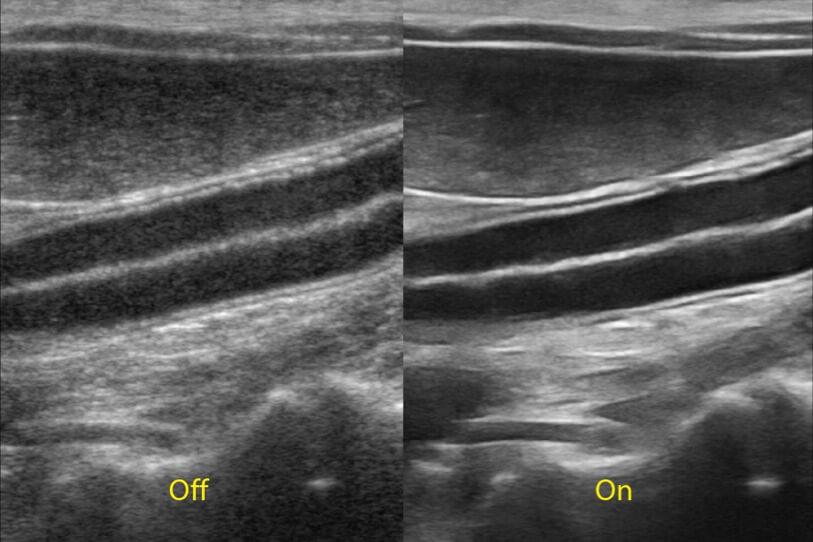

ProPet 70 進一步提升了微米成像算法,更加注重對基礎(chǔ)原始圖像的還原和保留,在有效減少斑點噪聲、增強組織邊界顯示的同時,避免過度優(yōu)化丟失真實的解剖信息。